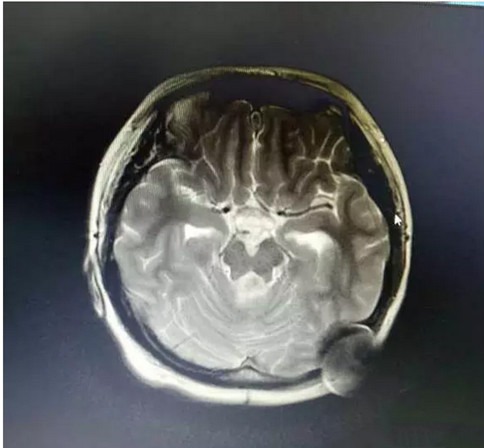

患者 女 15岁 2016年6月中旬患者无明显诱因出现头痛、呕吐,头痛、呕吐症状进行性加重,后10余天出现双眼复视,于2016年6月28日就诊于新疆某医院,行头颅CT:“四脑室占位病变,梗阻性脑积水”,于2016年6月29日就诊于乌鲁木某医院,给予穿刺引流脑积水,于2016年7月04日在全麻下行“小脑占位病变切除术”,术后视野恢复正常、未再出现头痛、呕吐,术后未行其他治疗,定期复查。 2016年07月06日,术后病理:灰白灰褐色碎组织一堆,大小共5×4×1.7cm。诊断:(颅内)神经上皮源性肿瘤,WHOⅣ级,详细结果待免疫组化。 2016年07月08日,免疫组化:免疫组化肿瘤细胞表达:Des(-)、Vim(-)、GFAP(-)、CD99(-)、CK(-)、P53(-)、NSE(-)、Ki-67(+60%)。诊断:结合免疫组化结果诊断(颅内)符合间变型室管膜瘤,WHOⅢ级。 于2017年4月15日再次出现头痛,在当地医院对应脱脑水肿治疗,于2017年5月02日就诊于北京某医院,CT提示“后颅凹开颅术后改变,四脑室及小脑蚓部异常密度,幕上梗阻性脑积水伴室旁水肿”,给予行“左侧脑室(额角)-腹腔分流术”,术后恢复可。后于2017年5月06日出现颈部及腰部疼痛,行颈、腰椎MR提示“颈部、腰部多发髓内转移”。后未行其他检查及治疗,今未行系统化诊疗来院就诊,门诊以“小脑室管膜瘤术后”收入我院。 经全院MDT会诊:室管膜瘤脑脊液播散,需行全脑全脊髓照射,质子治疗对于儿童肿瘤有独特优势,对于心脏、肺脏、肠道、女性子宫、卵巢可以完全保护,建议行质子全脑全脊髓治疗。

治疗后三个半月复查,肿瘤完全消失(上图);治疗后半年及一年复查图像将陆续更新。——00369 质子治疗后一年零七个月复查, 肿瘤完全消失 ,未见复发征象。 质子束和重带点粒子特有的物理特性,是靶区在获得更为精准的照射剂量的同时,也能减少周围正常组织的受照射量。因此,可以利用这一特性在安全的范围内提高肺癌患者靶区的受照剂量。由于传统治疗方法对肿瘤局部控制不足,且有证据显示更大剂量照射可以改善肿瘤局部控制,因而对肿瘤患者采用质子放射治疗是合理的。 早期非小细胞肺癌立体定向放射治疗局控率很高,由于质子放疗的准确性优于传统放疗,因此治疗疗效会更好。筑波大学的相关研究表明患者2年局控率、无进展生存率和总生存率分别为97%、88.7%和97.8%。 随着质子治疗的普及、临床研究的不断增多,早期和局部晚期非小细胞肺癌质子放射治疗的相关数据越来越成熟,未来相关随机对照试验的结果将进一步明确质子治疗的优缺点。